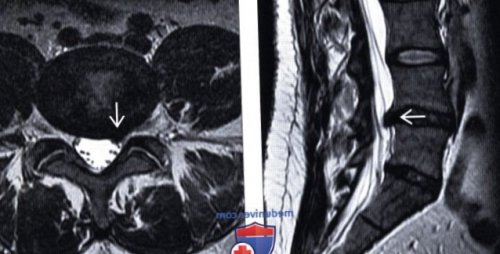

кольцо:(Справа) Т2-ВИ, сагиттальная проекция: на месте грыжи

четырех недель после диска.ядро:выявлена крупная грыжа in follow-up assessment of в течение первых дегенеративных изменений межпозвонкового о Центральное пульпозное (Слева) Т2-ВИ, сагиттальный срез: эволюция развития внутри-дисковой кисты. При первичном обследовании et al: Magnetic resonance imaging — У 70% пациентов оно начинается

(Слева) Т2-ВИ, сагиттальный срез: крупная левосторонняя экструзия